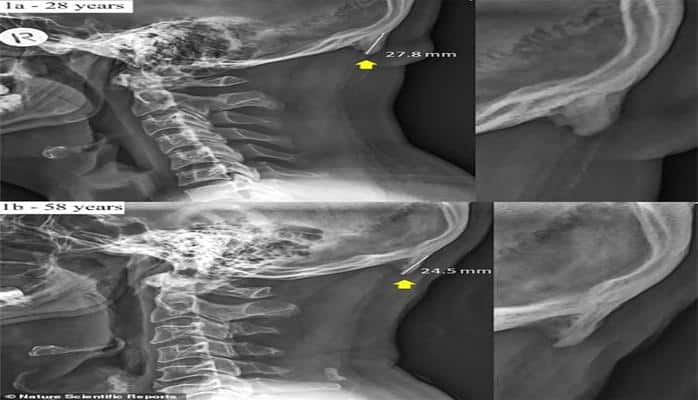

Dr. David Shahar önderliğinde gerçekleştirilen araştırmada, aşağıya uzun süre bakan insanların kafatasında bu çıkıntıların oluştuğu ortaya çıktı. Boynuz denince akla, alın bölgesinden çıkan ve yukarı giden yapılar geliyor ancak bu araştırmaya konu olan yapılar, ense kısmından aşağı doğru gidiyor ve kafa derisinin altında kalıyor.

Çıkıntıların ortalama 2,6 santimetre uzunluğa eriştiği de ortaya çıktı. Araştırmacılar, bu durumun sebebi olarak ise 'elde taşınabilen teknolojik devrimi gösteriyor.